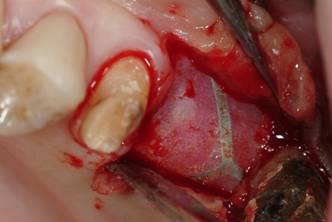

A buccal full thickness flap was harvested and the presence of a small OAF was verified. (Fig.3).

Figure 3

Flap elevation.

After the evaluation of OAF dimensions (Fig. 4), the surgical procedure was conducted by performing an incision on the bone tissue surrounding the lesion with bone drills and by harvesting a squared wedge bone on the alveolar ridge, in order to avoid the persistence of fibrotic tissue and to permit an adequate bleeding.

Figure 4

Demonstration of OAF existence by pin.